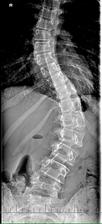

A na akú odchýlku sa jej po operácii podarilo dostať? Mala viac ako 60 stupňov a teraz?

6 a 8 stupňov